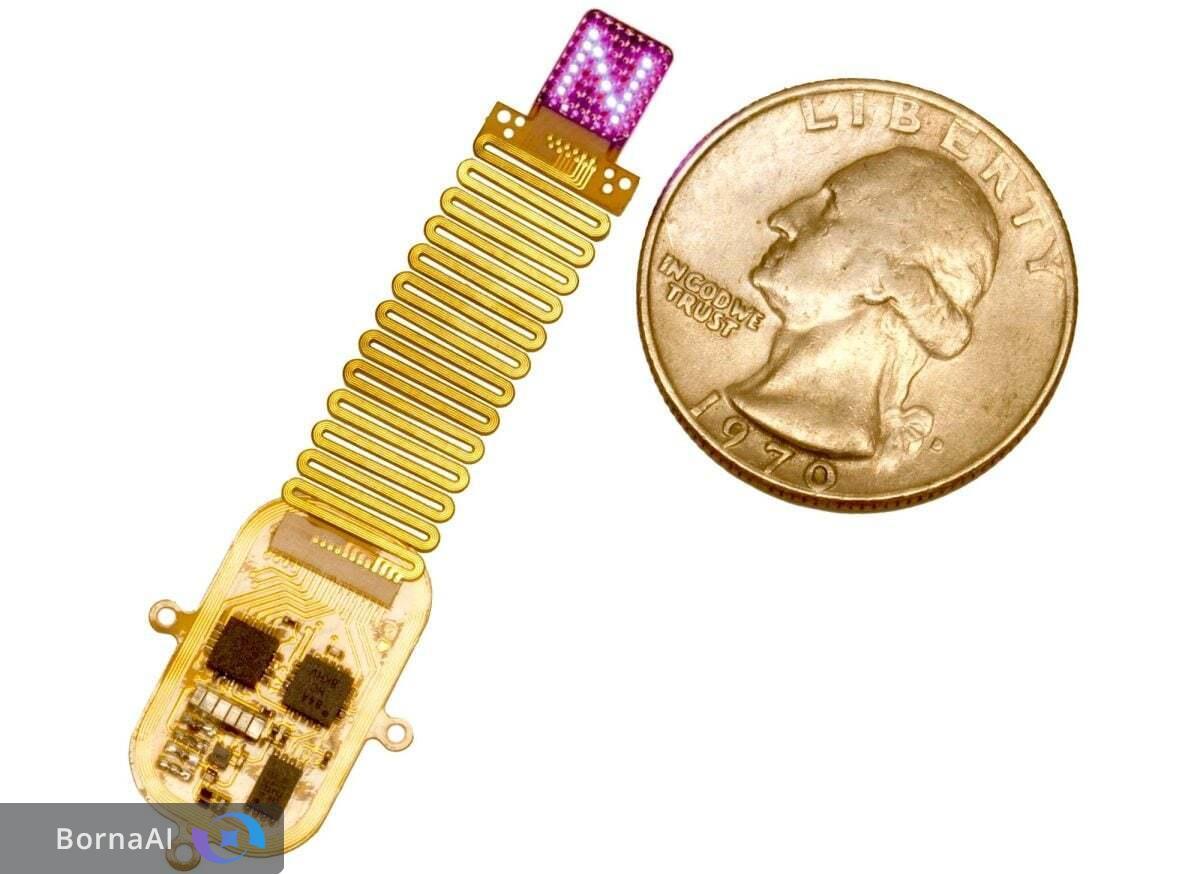

اکنون تیمی پژوهشی به سرپرستی ماریوس جورجیادیس، مدرس تصویربرداری عصبی روشی ساده، مقرونبهصرفه و دقیق برای آشکارسازی این شبکههای پنهان توسعه داده است. این روش که تصویربرداری محاسباتی نور پراکنده (Computational Scattered Light Imaging – ComSLI) نام دارد که در نشریه Nature Communications معرفی شده است.

ComSLI با تکیه بر رفتار فیزیکی ساده نور این محدودیتها را برطرف میکند. هنگامی که نور از ساختارهای میکروسکوپی عبور میکند الگوی پراکندگی آن به جهتگیری این ساختارها وابسته است. با چرخاندن جهت تابش نور و تحلیل تغییرات پراکندگی جهت الیاف در هر پیکسل تصویر مشخص میشود.

این روش تنها به یک منبع نور LED چرخان و دوربین میکروسکوپ نیاز دارد و سپس الگوریتمهای محاسباتی نقشههایی رنگی از توزیع جهت و تراکم الیاف تولید میکنند.